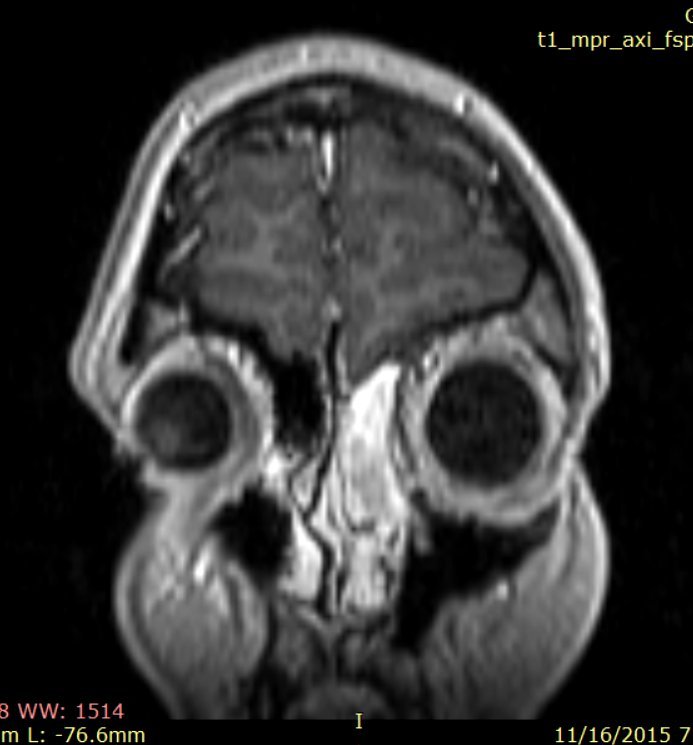

CT cu substanţă de contrast efectuat la finalul intervenţiei confirmă rezectia completă a tumorii (fig. 5)

Fig.5: control CT craniocerebral postoperator final